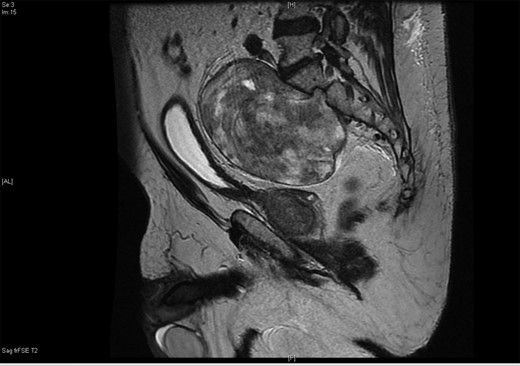

A 71-year-old asymptomatic gentleman with known history of colonic polyps underwent a follow-up surveillance colonoscopy through the BCSP. He had a background of type 2 diabetes mellitus, ischaemic heart disease and diverticular disease. Colonoscopy revealed a 1-cm firm polypoid mass at the ano-rectal junction (Fig. 1). Subsequent endoscopic mucosal resection was performed and the tissue was sent for histological analysis. This confirmed a tubulo-villous adenocarcinoma. As per national guidelines the patient underwent a staging computed tomography (CT) scan. This revealed a 10 × 15 cm homogenous mass arising from within the pelvis (Fig. 2). The mass appeared to be continuous with a neural foramen arising from the sacrum. Further imaging confirmed the mass extending into sacral segment S1 inferiorly, lumbar segments L4 superiorly and the bladder anteriorly. A regional multidisciplinary team discussion concluded that abdominoperineal resection (APR) was the most appropriate surgical approach for removal of both pathologies in their entirety.

The 10 × 15 cm pre-sacral pelvic mass on sagittal contrast CT.

The upper and mid-rectum were successfully mobilized from anterior to posterior behind the seminal vesicles using circumferential dissection techniques. Full rectal mobilization was made complex by the large 10 × 15 cm pre-sacral mass obstructing dissection planes down to the pelvic floor posteriorly. The sigmoid colon was subsequently divided ∼15 cm above the peritoneal reflection and retracted anteriorly to allow access to the tumour (Fig. 3).